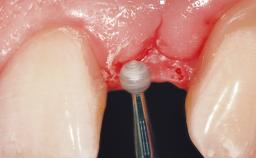

Late Placement of an Implant in a Maxillary Left Central Incisor Site

Soft Tissue Grafting Simultaneous

Soft Tissue Contour and Volume Slightly compromised